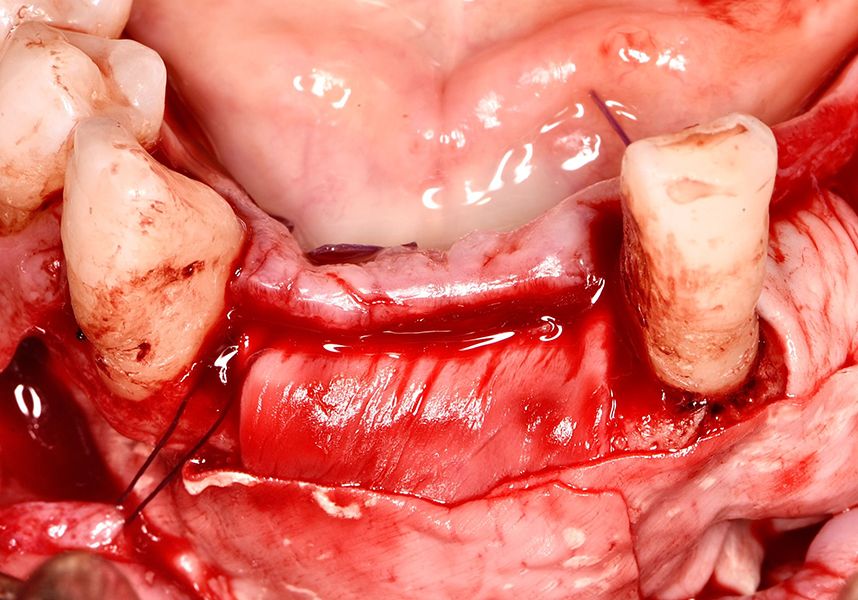

To treat the defect, bone regeneration was carried out simultaneous to the surgical process, with an autologous bone graft from the patient. In the internal part of the graft we used autologous cortical bone obtained by scraping (Safescraper) and from the biological drilling, at low revolutions and without irrigation, from the other implant beds. In the external layer of the regeneration we used a xenograft (Genoss, Osteogenos) and this was covered with a reabsorbable collagen barrier membrane (Evolution STD, Osteogenos).

The membrane was sutured with PGA reabsorbable suture to the periosteum to secure it, thus avoiding subsequent reentry to remove fixings such as tacks.